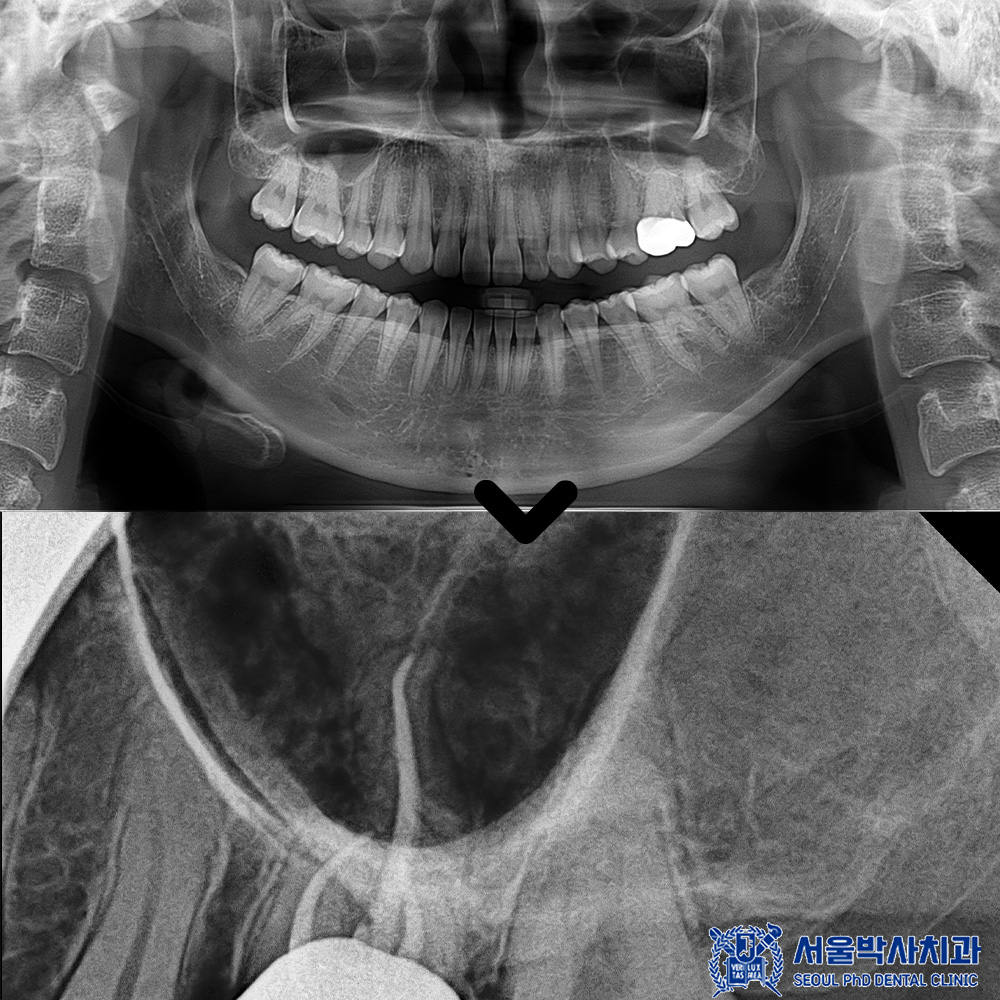

파노라마를 촬영하여 확인해 보니,

뿌리 쪽에 염증이 있는 것을

볼 수 있었는데요.

CT상에서도 뿌리 끝 부위에

염증 병소가 보다

명확하게 확인되었습니다.

파노라마에서는 평면적으로 보였다면,

CT 촬영을 통해 염증의 위치와 범위,

주변 뼈 손상 정도까지

입체적으로 확인할 수 있었고,

그 결과 해당 치아는 신경치료가

필요한 상태임을 판단할 수 있었습니다.